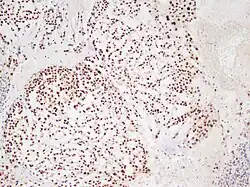

Chordome sind langsam und destruktiv wachsende Tumoren der Wirbelsäule und der Schädelbasis, die in etwa 10 % der Fälle metastasieren.

Chordome werden manchmal zu den Knochentumoren gezählt, obwohl sie nicht aus Knochengewebe stammen, sondern aus Resten der Chorda dorsalis (Notochordoa) an den Enden der Wirbelsäule. Damit lassen sich auch ihre Hauptlokalisationen, nämlich Schädelbasis und Steißbein, erklären. Die ICD-O-3 klassifiziert sie unter die Sonstigen Tumoren des Nervensystems (Nr. 937).